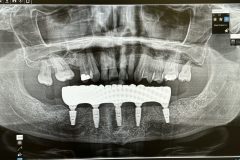

Implants placed using a digitally planned stackable surgical guide following alveolectomy, ensuring ideal positioning and a stable foundation for full-arch restoration.